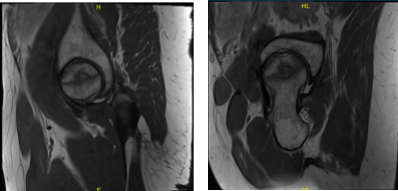

She presented MRI results for both of her hips that showed mild common hamstring tendinosis with a small intrasubstance tear and surrounding edema at the ischial tuberosity. Extensive avascular necrosis of the right femoral head. Degenerative changes in the lower lumbar spine for her left hip.

Extensive avascular necrosis involving the majority of the right femoral head and surrounding bone marrow edema extending into the femoral neck. Crescentic subchondral fracture line is seen medially without articular collapse or fragmentation.

There are mild osteophytic changes of the right femoral acetabular joint and a moderate joint effusion. Mild gluteus minimus tendinosis without a tear, for the right hip.

MRI Left hip non-contrast

MRI Right hip non-contrast